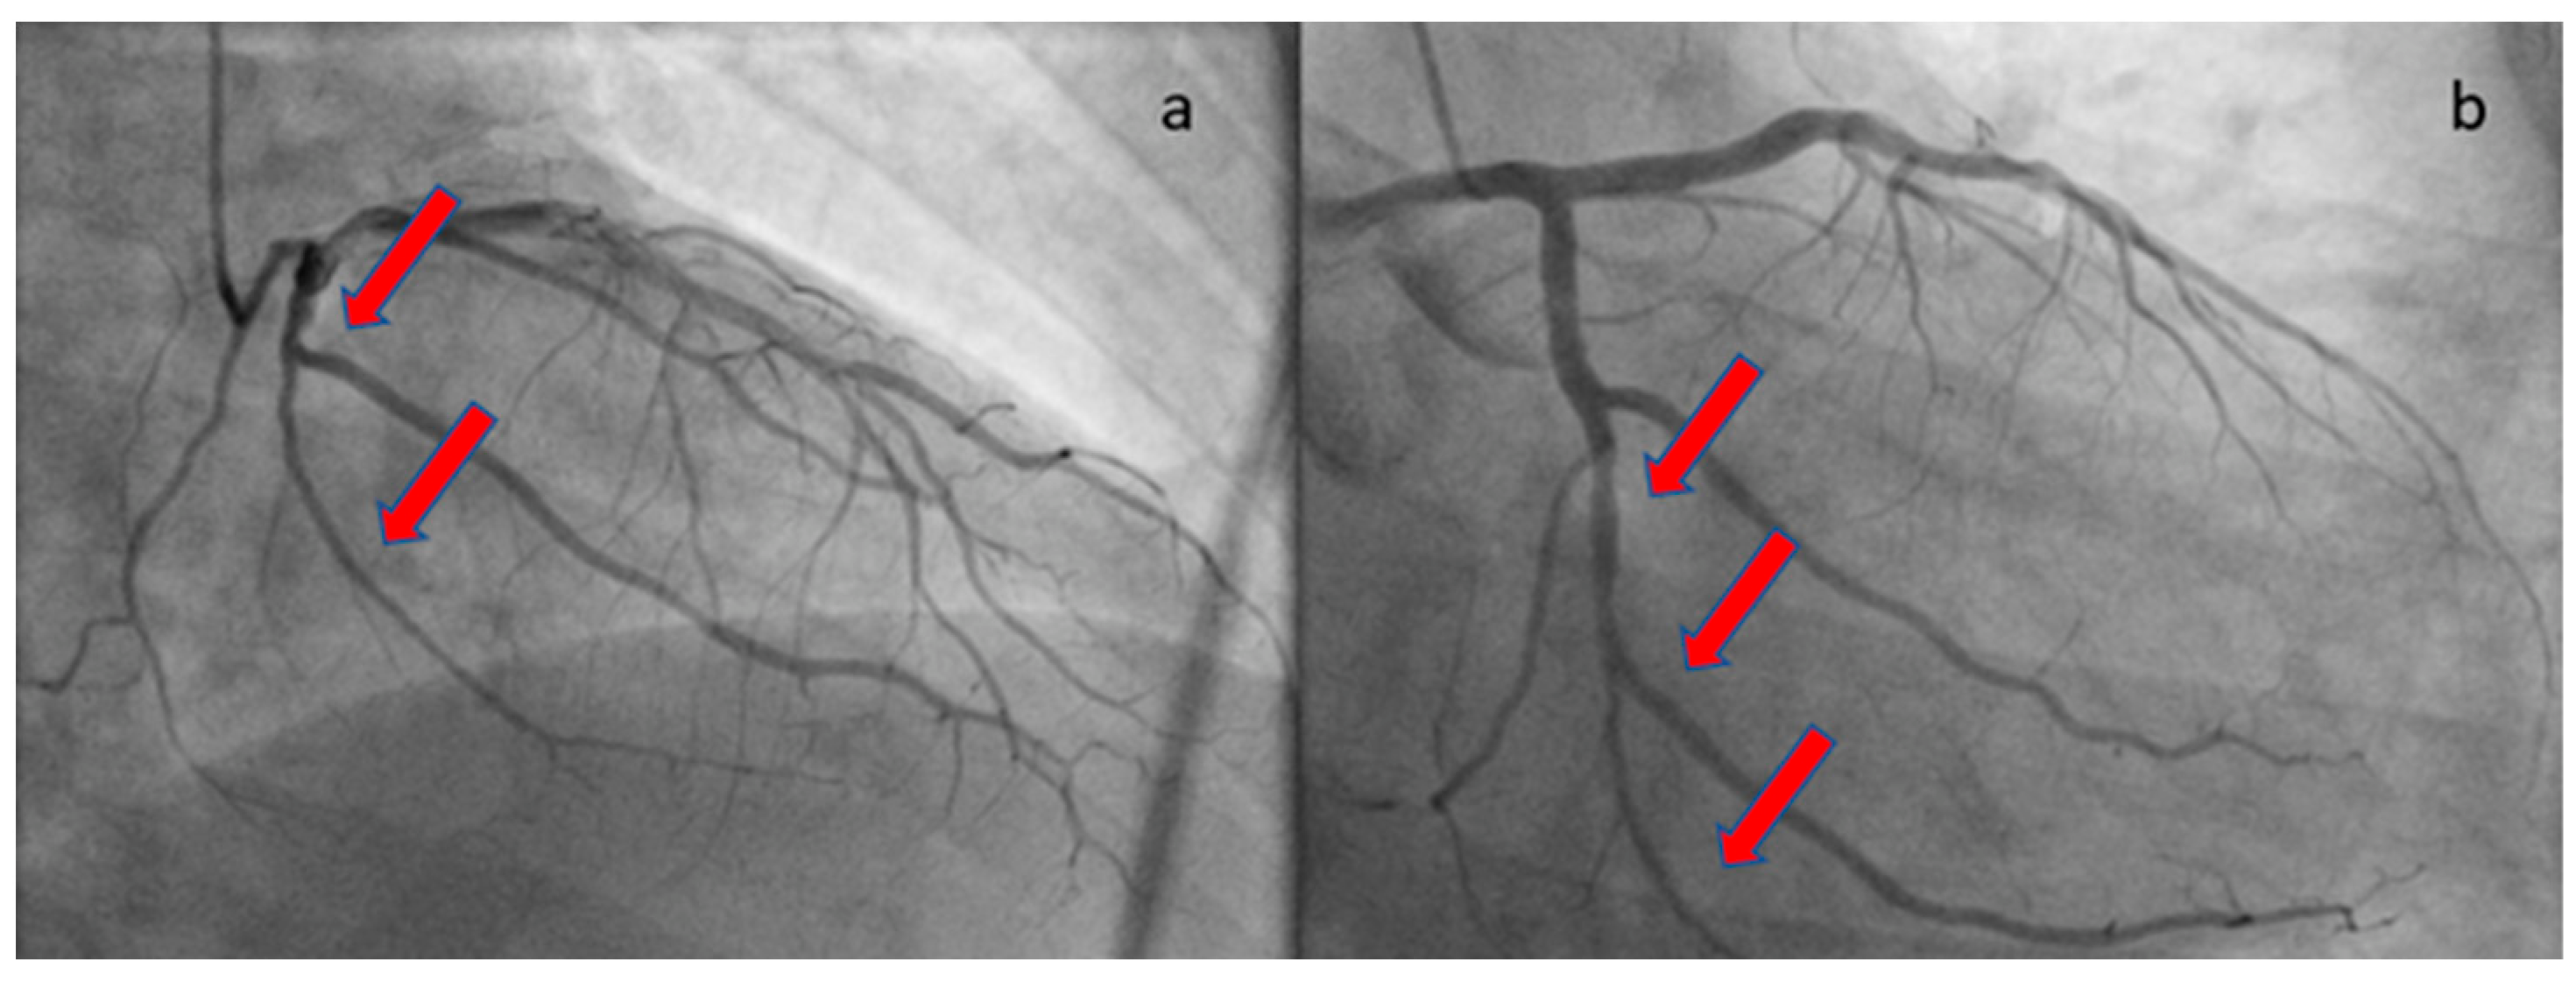

The patient was loaded with aspirin (ASA) 325 mg and ticagrelor 180 mg and transferred to the catheterization laboratory, where emergent coronary angiography was performed via right radial access. During contrast injection in the left coronary system, a long smooth 70–80% stenosis was revealed along the mid portion of the left circumflex artery (LCX) extending to the distal part of the vessel, including an obtuse marginal branch (Figure 2). Despite intracoronary administration of nitroglycerin, the narrowing along the vessels remained unchanged; hence, we proceeded with intracoronary imaging using optical coherent tomography that revealed SCAD (Figure 3). The remainder of the coronary tree was normal.

Figure 2. Coronary angiography revealing a long, smooth lesion in LCX. The red arrows show the long lesion. (a) RAO cranial angiographic view; (b) RAO caudal angiographic view.